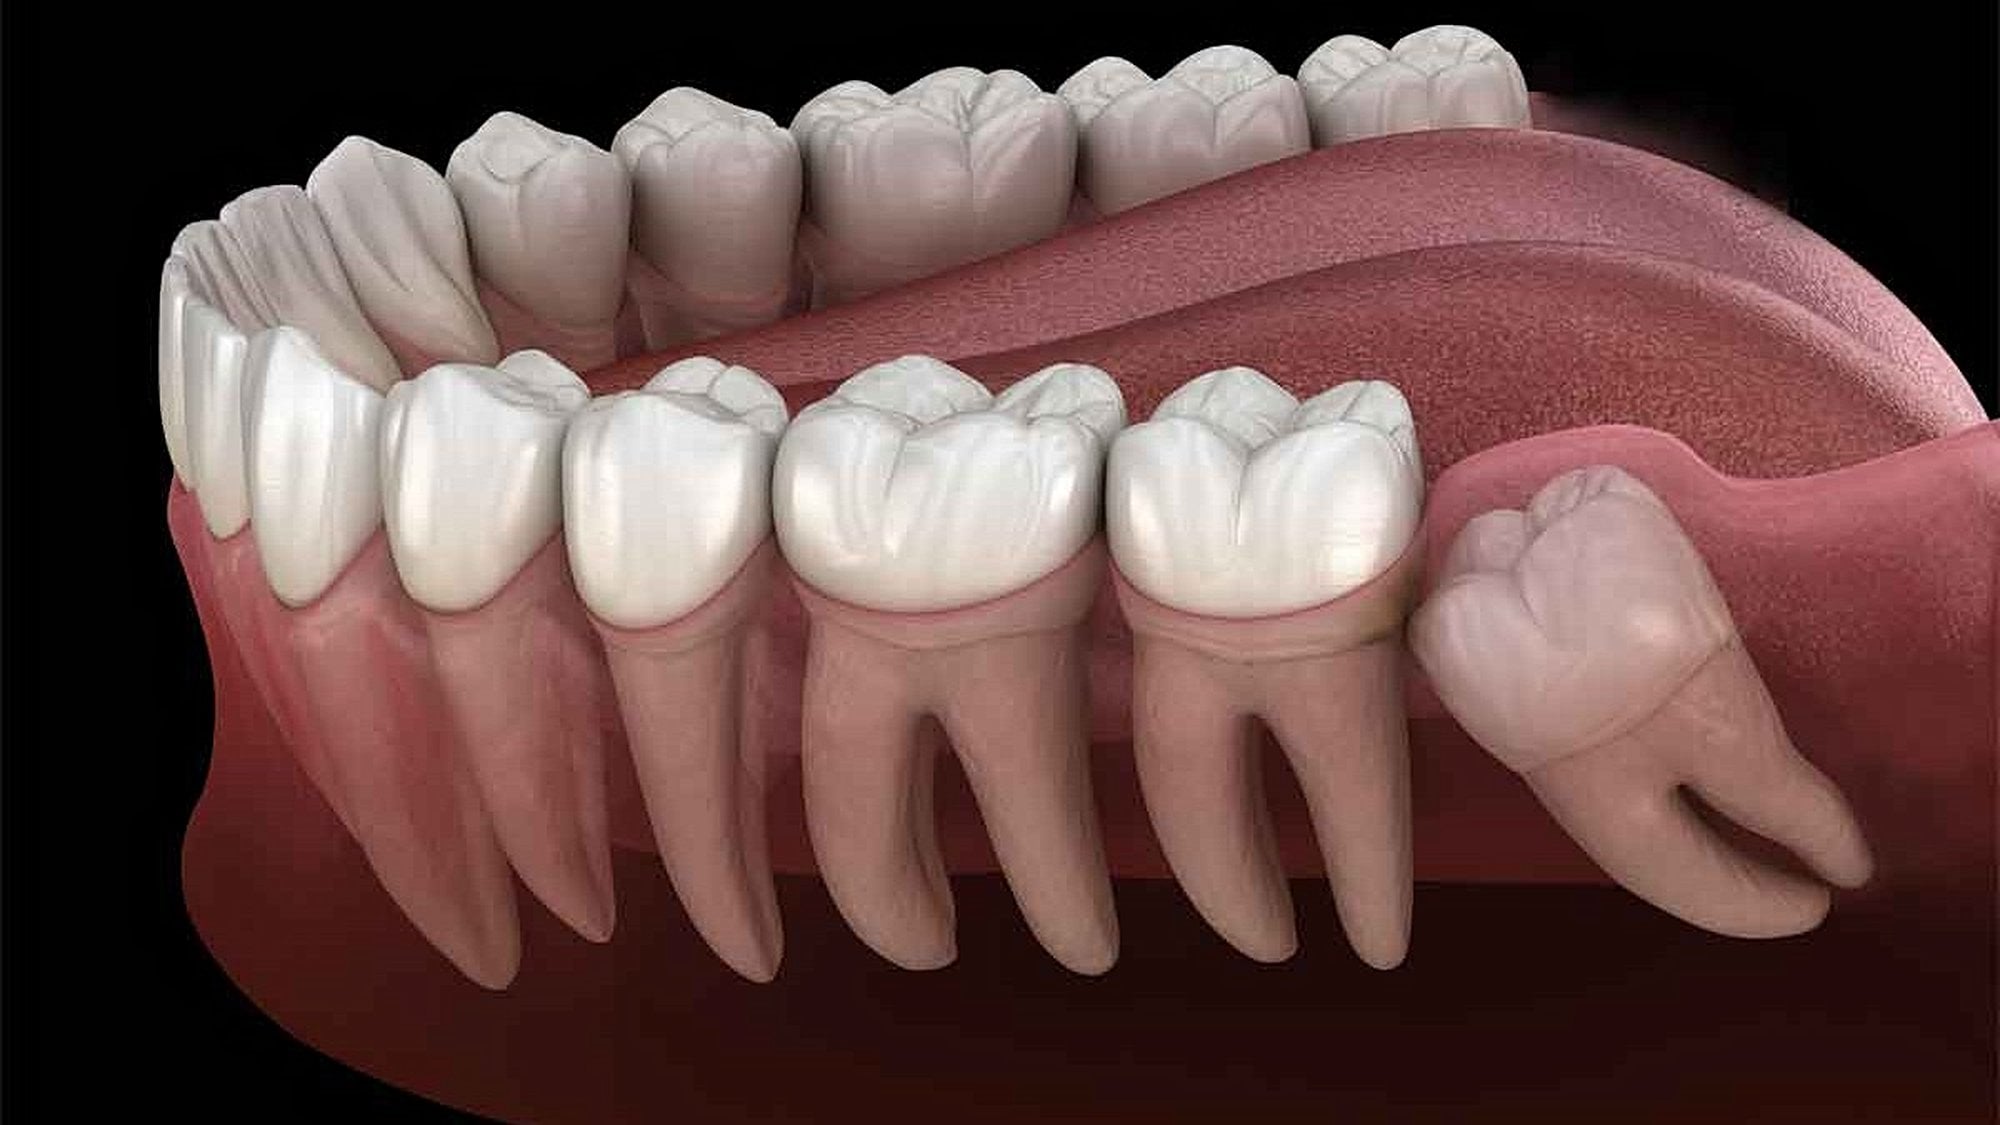

Yirmi yaş dişlerinin sıklıkla gömülü kalırlar, çıktıkları zaman doğru şekilde çıkmazlar ve diğer dişlere sürtünerek onların yapısını bozabilirler. Bu nedenle de ağrı ve enfeksiyona neden oldukları bilinmektedir. Bunun haricinde ise hiçbir işlevleri bulunmamaktadır. Dolayısıyla ağrıya neden oldukları zaman, diş hekimleri tarafından çekilerek hasta rahatlatılabilmektedir. 20 yaş dişleri çekilen kişilerin ağız fonksiyonlarında hiçbir azalma olmamaktadır. Aşağıda bu dişleri görmektesiniz:

Tüm bunlar sonucunda etkilenen organlardan biri de, çene ve diş yapımızdı. Beynimizin büyüyebilmesinin bizlere avantaj sağlamasından ötürü, beyne yer açmak adına ve diyetin de değişmesiyle birlikte çene yapımız küçülmeye başladı. Artık eski güçlü ve vahşi ağızlara ihtiyacımız azalmaya başlamıştı. Otlara göre sindirimi çok daha kolay olan et için fazladan dişlere ihtiyacımız kalmamıştı. İşte bu yüzden de fazladan dişler üretmeye harcanan enerji, başka alanlara harcanabilirdi. Zaten çenenin küçülebilmesi için en dıştan başlayarak dişlerden fedakarlık etmek avantaj sağlamaktaydı.